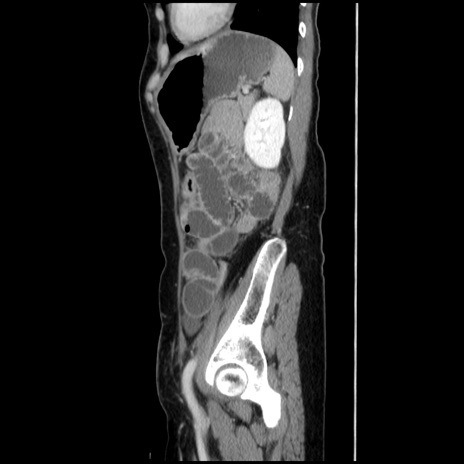

症例32(矢状断像)

【症例】40歳代 女性

【主訴】上腹部痛、嘔気・嘔吐

【現病歴】約9時間前頃から急に上腹部痛、嘔気、嘔吐が出現。改善しないため救急要請。

【既往歴】子宮頚癌(広汎子宮全摘術、放射線療法)、腸閉塞

【身体所見】腹部:平坦、軟、腸雑音亢進、上腹部を中心に腹部全体に圧痛あり。

【データ】WBC 8400、CRP 0.03